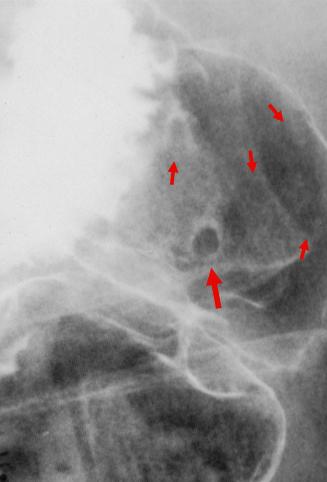

A case of multiple ectopic gastric mucosas in the duodenal bulb.

[Image-ID:11310]

종양양 병변/이소성 점막

십이지장/구부

X-P

1~9